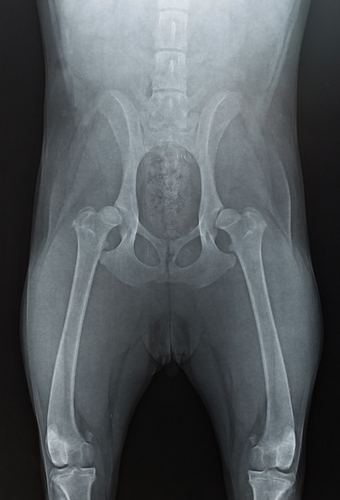

Hip dysplasia (HD) refers to the malformation of the hip joint: instead of a round femoral head fitting smoothly into a deep acetabulum, the joint contains a shallow socket and irregularly shaped ball. These malformations cause uneven contact between the joint surfaces compromising the joint stability and eventually deforming the bone and causing pain. This laxity in the joint also erodes the joint and causes inflammation and bone remodelling to occur, which in turn leads to arthritis or degenerative joint disease. HD can be unilateral or bilateral.

hip_full_flexionHip dysplasia is one of the most common skeletal diseases seen in dogs. Gender does not seem to be a factor, but some breeds are more likely to have the genetic predisposition for hip dysplasia. Large and giant breeds are most commonly affected, including the Great Dane, Saint Bernard, Labrador, Rottweiler and German Shepherd.